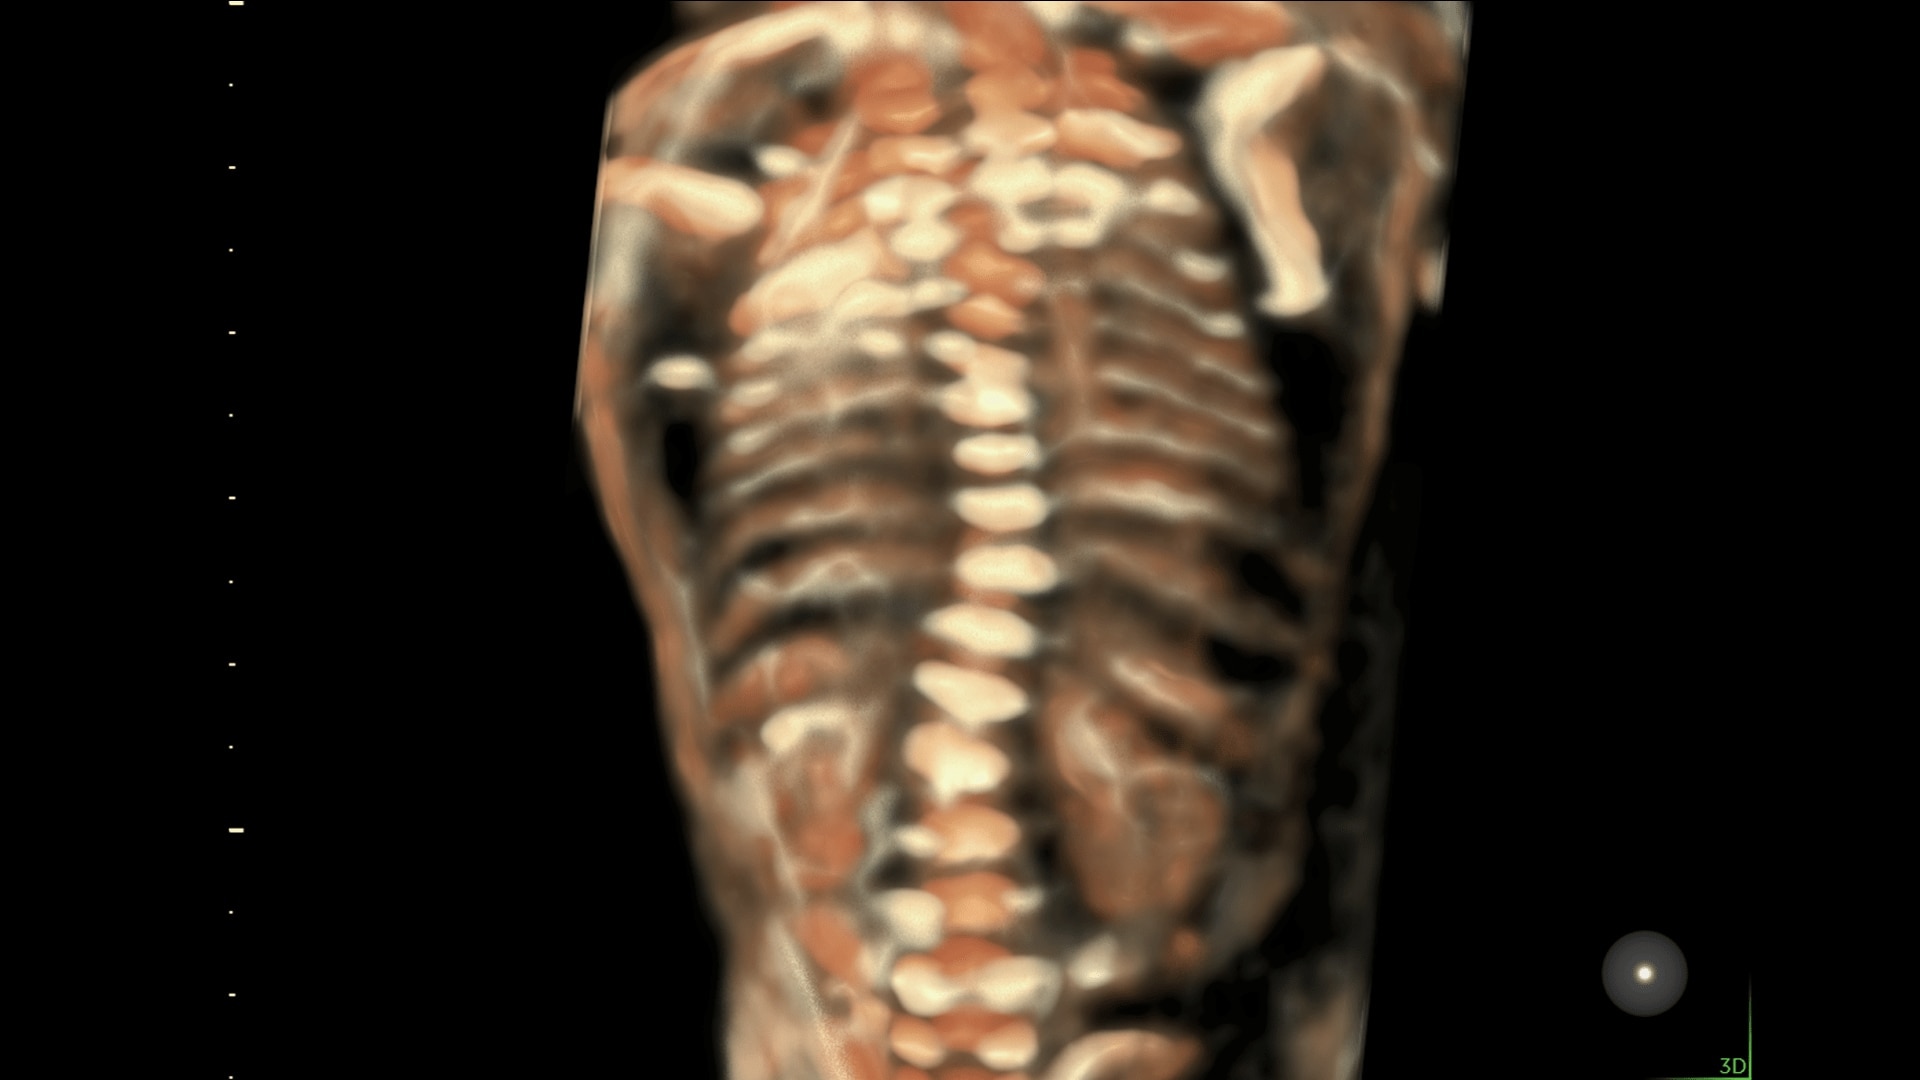

Enhanced Volume Imaging

Deliver next generation 3D/4D & Color images with HDlive Studio+

Unique Probe Technology

Obtain high resolution images with advanced probe technology - eM6C, RIC6-12, and RM7C